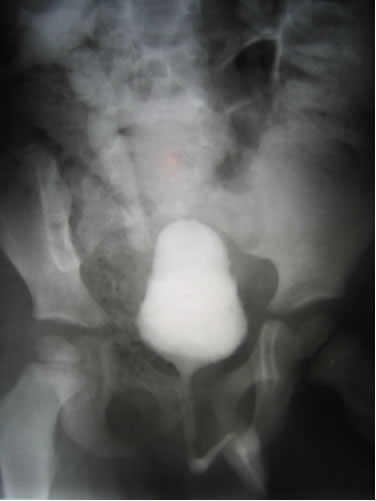

Цистография